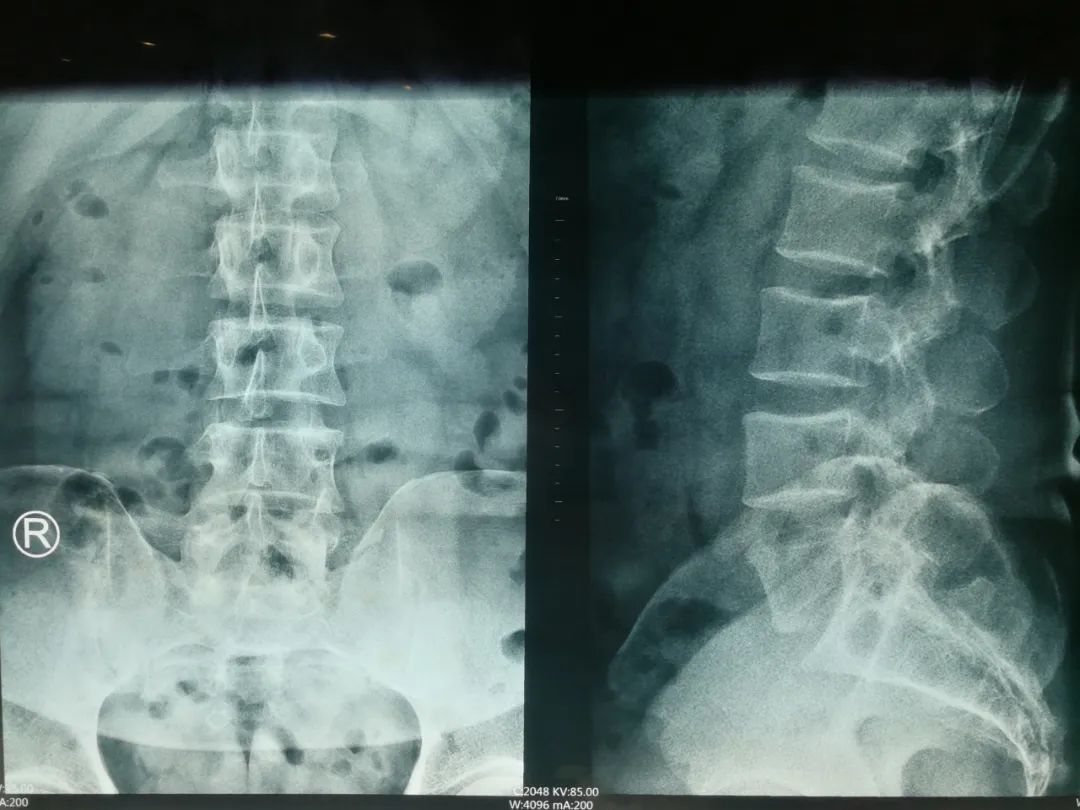

阅片

刘先生是典型的“腰椎间盘突出症(L5S1左后突出)”,伴有椎管狭窄的间歇性跛行症状,专科查体时最主要的体征是: